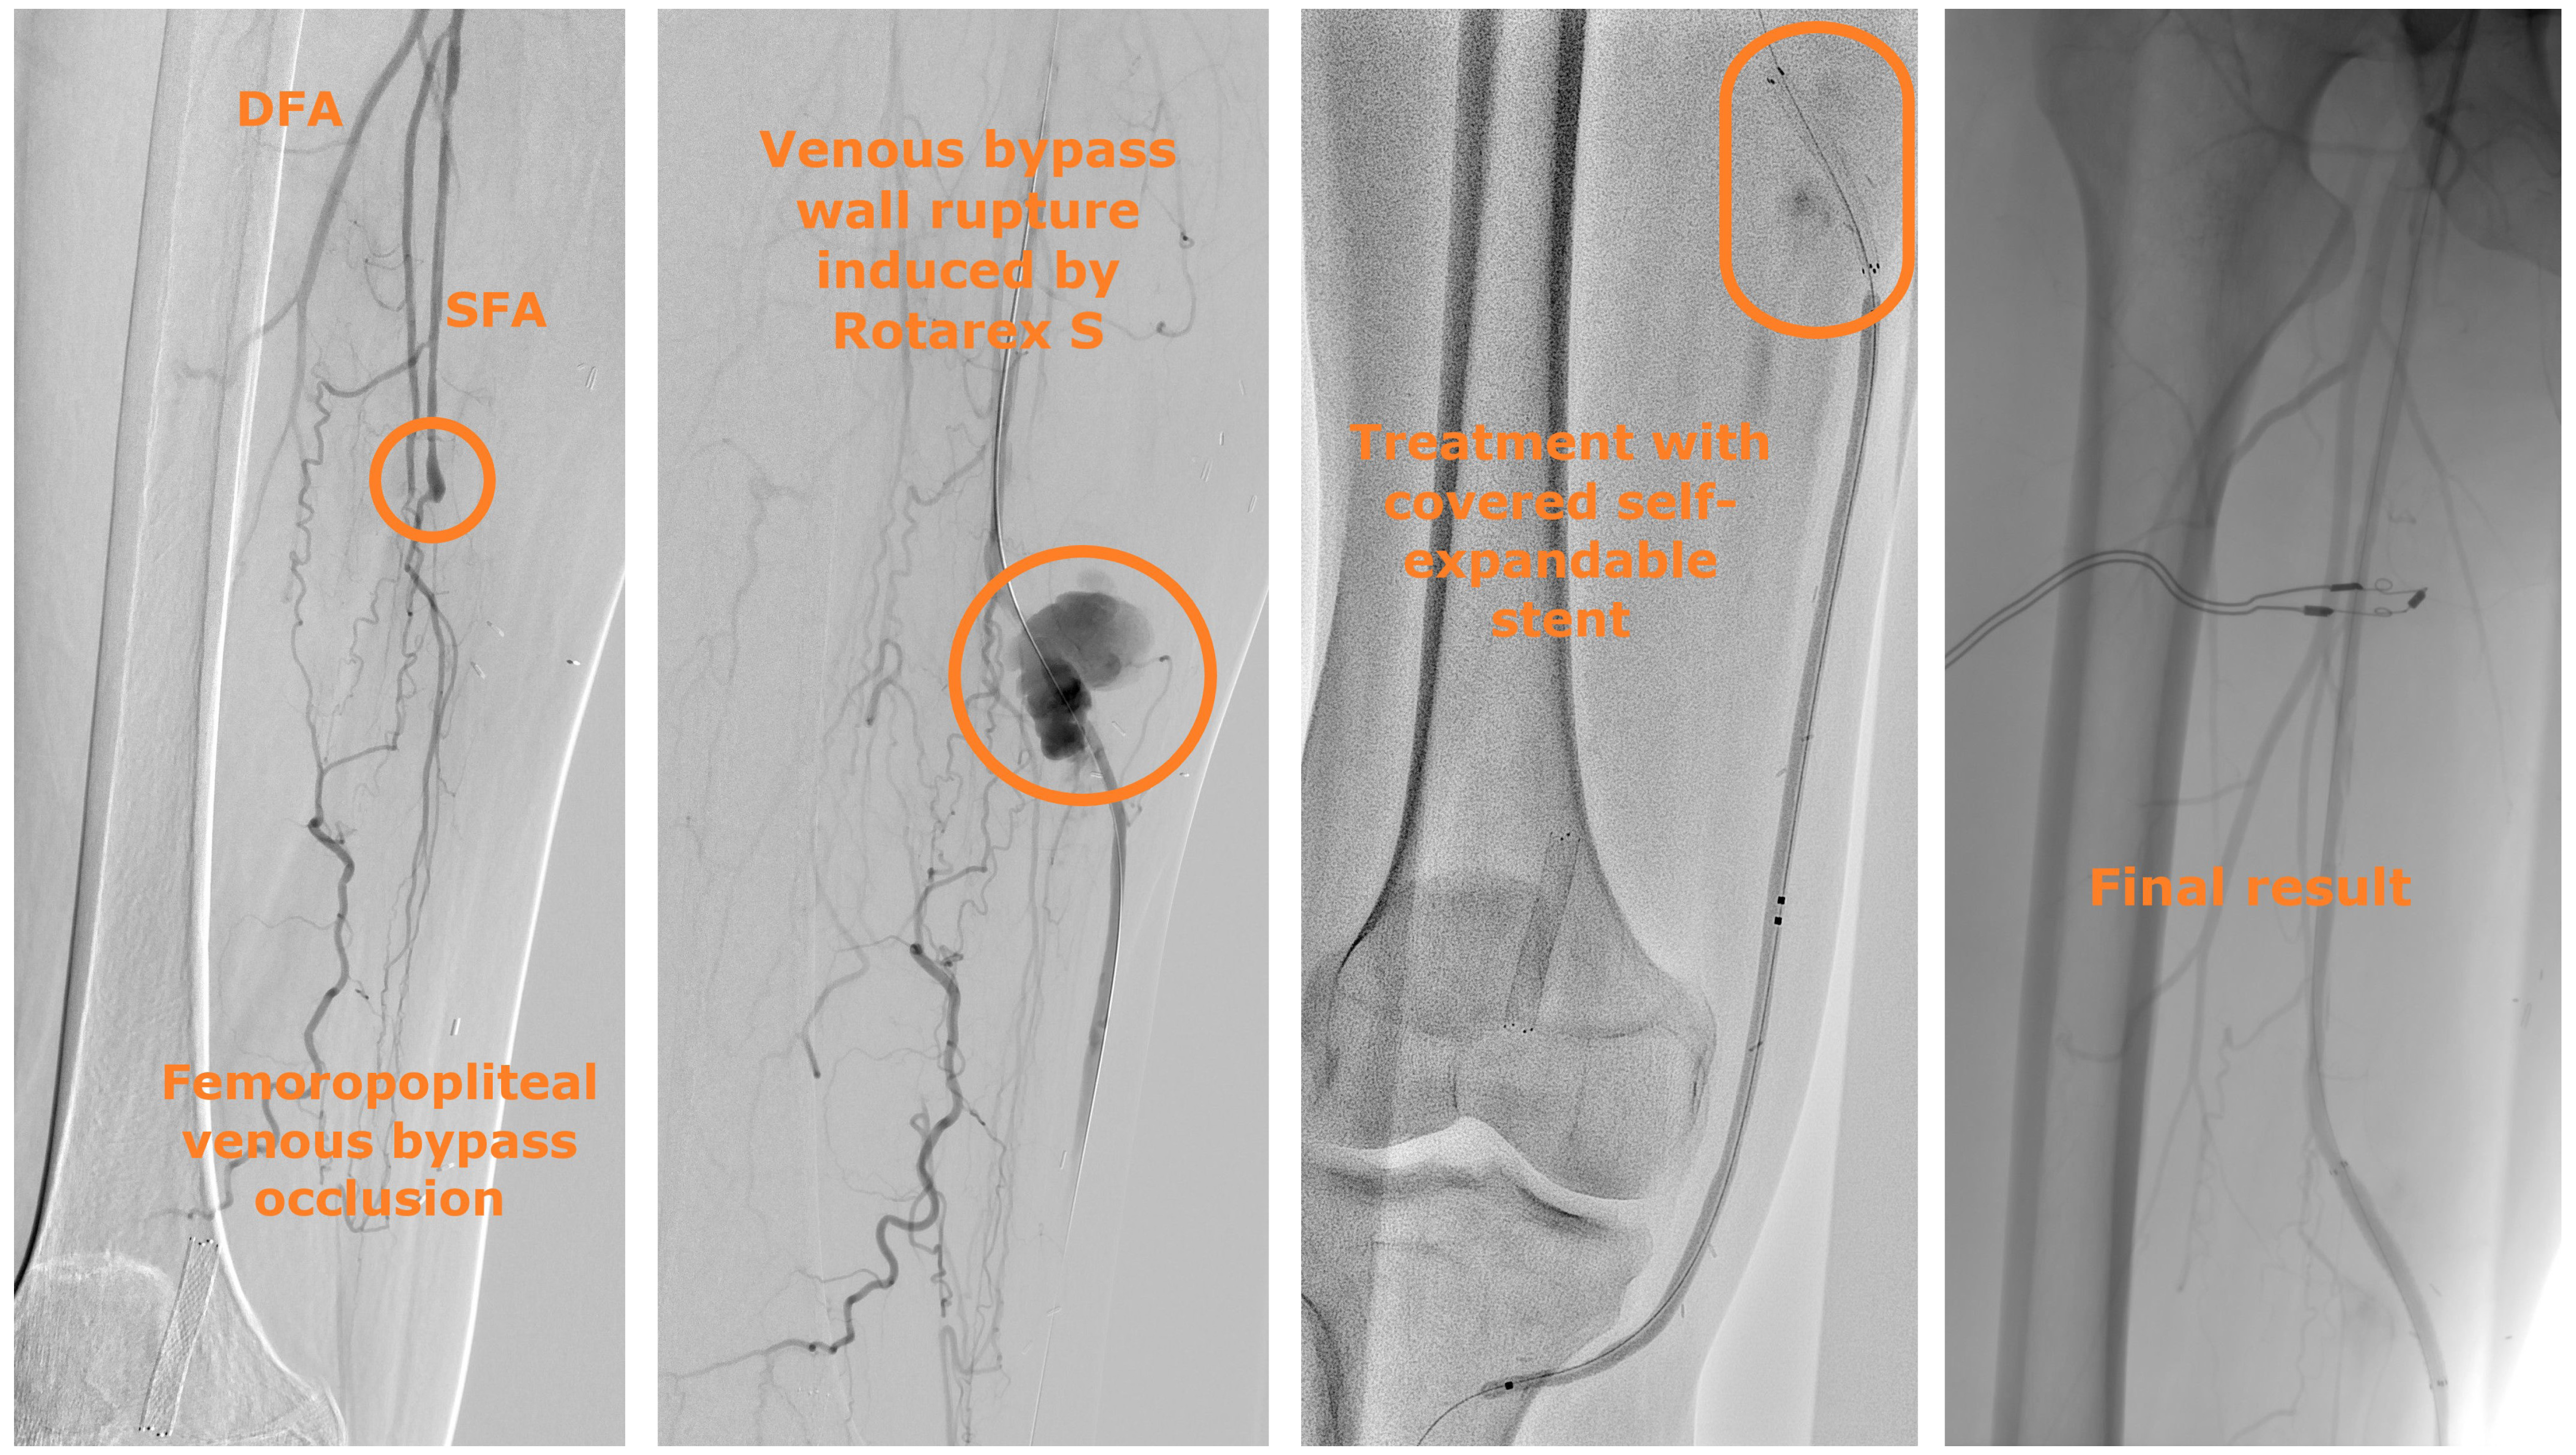

A 44-year-old man presented with chronic limb-threatening ischemia. He had rest pain and first-toe necrosis (Rutherford classification stage 5). Computed tomography angiography (CTA) highlighted thrombosis of a femoropopliteal venous bypass that was performed more than 2 years earlier. An atherothrombectomy device was used to recanalize the bypass (Figure 1). The procedure was complicated by bypass rupture and acute hemorrhage. A 5-mm x 50-mm Viabahn self-expandable covered stent (Gore) was promptly deployed to successfully stop the bleeding.

Abbreviations: DFA, deep femoral artery; SFA, superficial femoral artery.

When an arterial wall rupture induced by atherectomy occurs, the treatment is driven by the rupture characteristics; our treatment algorithm is shown in Figure 3. When the perforation is not associated with bleeding or is associated with low-flow bleeding, prolonged balloon angioplasty is typically sufficient. When the rupture is associated with high-flow bleeding, prompt deployment of a self-expandable covered stent is indicated.